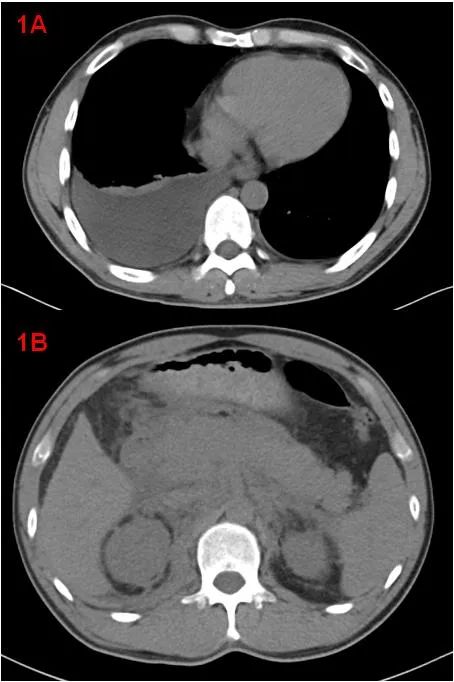

中年男性,體檢發(fā)現(xiàn)“雙腎積水”來診,余無明顯不適。CT示雙側胸腔積液、右肺膨脹不全(圖1A);胰腺腫大、胰周滲出,腹腔少量積液、腹膜、網(wǎng)膜增厚,腹膜后軟組織增厚(圖1B);考慮自身免疫性胰腺炎?腹膜后纖維化?